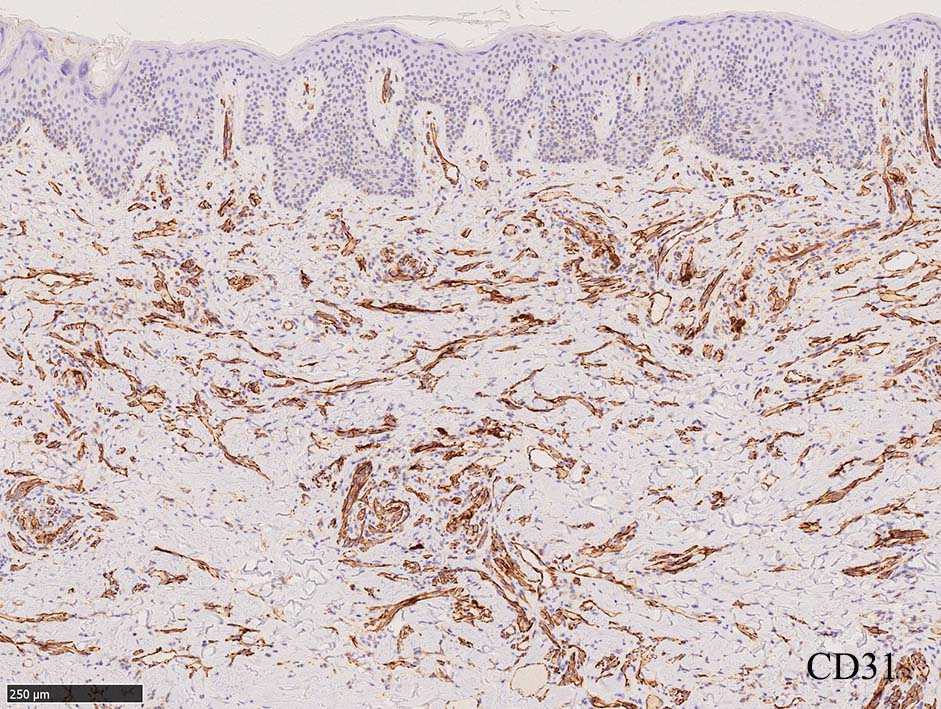

免疫染色, 分子病理学的検査

増生細胞はCD31, CD34, Factor Ⅷ, D2-40などが陽性を示す.

細血管周囲に血管内皮様の紡錘形細胞が増生, 一部に赤血球をいれた裂隙の形成がある. 細胞の異型はみられず, mitosisの増多もない. hemosiderin-laden macrophageが散在する.

病変は真皮内に現局している. 初期斑状病変に相当すると考えられる. 本例では, 特徴とされる形質細胞浸潤増加はみられない.